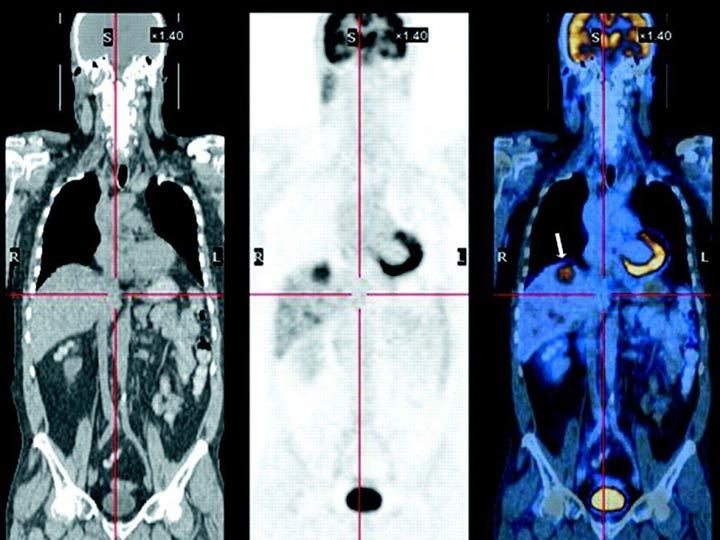

How does a PET scan work?

Detects pairs of gamma rays emitted by postitron-emitting radionuclide = introduced into body on biologically active molecule

Use of FDG on PET scans - what is it, how does it work, what is it used to visualise + which cancers are show up well?

Fludeoxyglucose = conc of tracer imaged will indicate metabolic activity as it corresponds to regional glucose uptake Used to explore possibility of metastasis

Good for lymphomas + lung cancer

How is a PET scan visualised?

Superimposed on CTs, which give anatomical landmarks